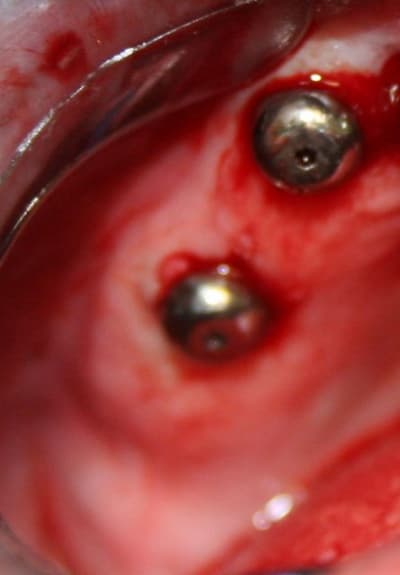

Pour ceux que ca interessent, et parce qu on a m a demandé des cas supplémentaires dans le sujet 23 implants rehabilitation totale, voici un autre cas d implantation immédiate avec la technique minimalement invasive et condensation grace aux forets.

Le patient a reçu un traitement il y a dix ans dans le maxillaire et dans le 4eme quadrant.Comme on peut le voir j´ai du extraire quelques dents au maxillaire: 35 37 et 45.

Le septum de la 37 a été foré avec un foret conique 3 faces.

J ai planté à 60 Ncm sans fracturer le septum.Juste après l opération , les prep caps en zircon ont été cémenté.La restauration définitive 34 jusqu` à 37 été fixé 2 semaines après l implantation avec implantlink (detax). Après un an, le bridge a été retiré facilement pour voir l´état de la gencive et faire une radio de contrôle.On la re ossifiction est satisfaisante et que la gencive "aime" le zircon.

Le bridge a ensuite été recémenté sans correction nécessaire du bridge.